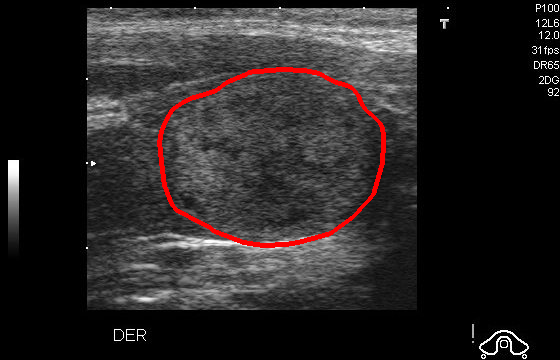

Reduce Contrast

Ultrasound GMAIMMbench Disease Diagnosis

Reduce Contrast - L0 (Original)

L0

L0 (Original)

Reduce Contrast - L1 (Moderate)

L1

L1 (Moderate)

Reduce Contrast - L2 (Severe)

L2

L2 (Severe)

Question

Given that this is a UltraSound image, which option would be the most fitting for the marked area?

A thyroid nodule B cardiomegaly C brain hemorrhage D diabetic macular edema E esophageal cancer

Ground Truth: A. thyroid nodule